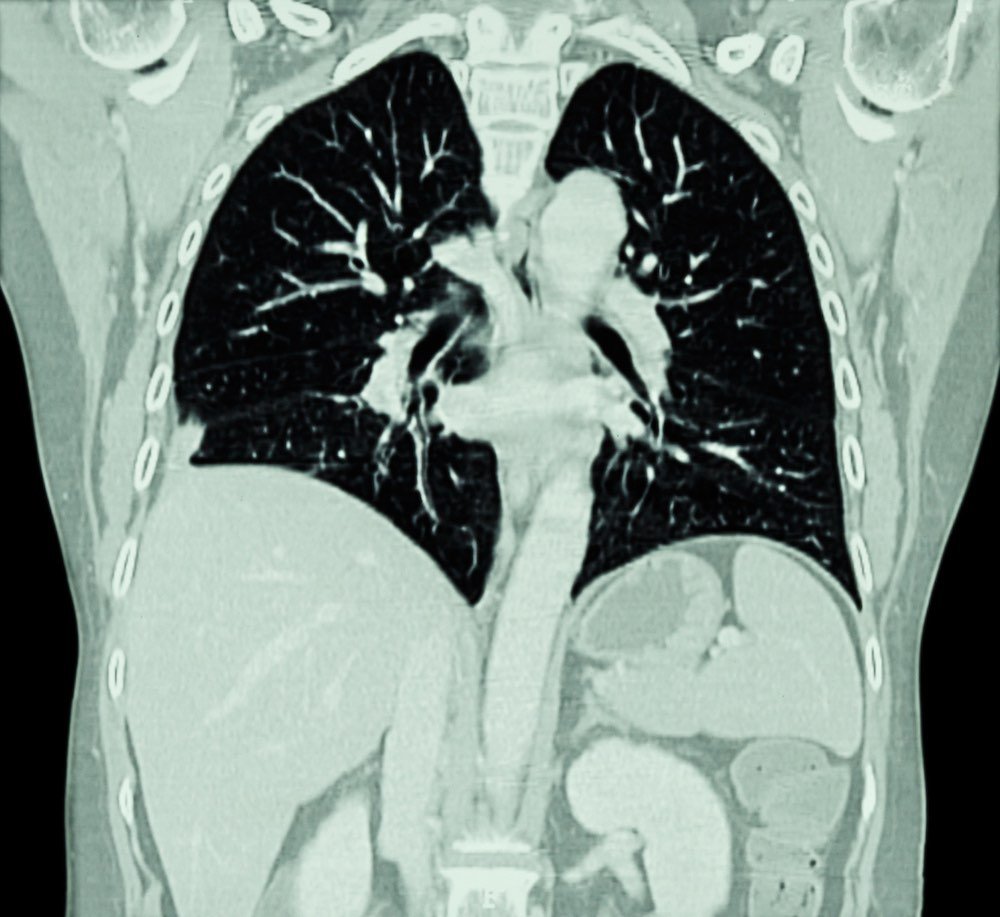

Le TAC e i tumori

Le TAC comuni potrebbero causare fino al 5% dei nuovi casi di tumore, secondo uno studio

L’articolo ci racconta dello studio, la cui prima firmataria è la professoressa Rebecca Smith-Bindman, dell’Università della California a San Francisco, che ha analizzato i dati relativi a 93 milioni di tomografie computerizzate (TAC) eseguite negli Stati Uniti nel 2023.

Utilizzando modelli di rischio basati su dati del National Cancer Institute, i ricercatori hanno stimato che queste scansioni potrebbero essere associate a circa 103.000 futuri casi di cancro, pari a circa il 5% di tutte le nuove diagnosi annuali negli Stati Uniti.